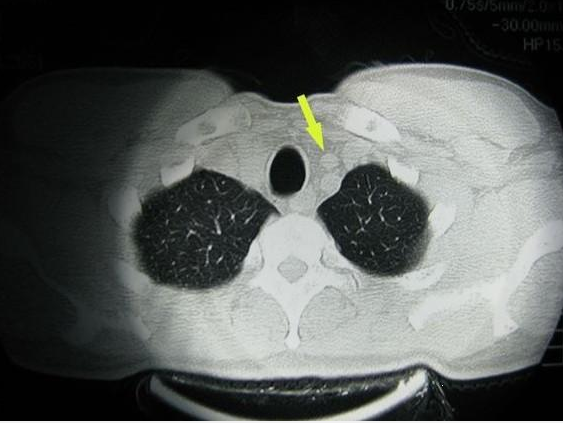

胸腺是人體重要的免疫器官,是淋巴系統(tǒng)的一部分,其功能是將部分淋巴細胞分化成T淋巴細胞。胸腺和人體其他器官一樣,可發(fā)生良性或惡性腫瘤,較常見的是胸腺瘤,其他腫瘤或類腫瘤疾病還有:胸腺癌、胸腺囊腫、胸腺脂肪瘤、胸腺增生等。